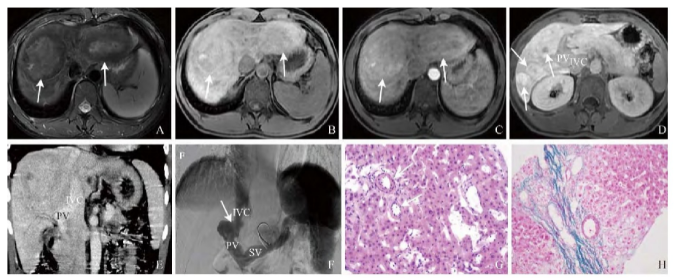

腹部超声提示:肝内多发占位性病变,门静脉异常。钆塞酸二钠增强MRI及腹部增强CT(图1A~E)均提示肝内多发局灶性结节增生可能,Abernethy畸形可能。数字减影血管造影(DSA,图1F)提示Abernethy畸形Ⅱ型。行肝脏穿刺活检明确占位性质,病理(图1G~H)诊断为局灶性结节增生。特殊染色及免疫组化显示:网织(+),胶原纤维(+),谷氨酰胺合成酶(+,强弱不等),细胞角蛋白19(细胆管+),细胞角蛋白7(部分肝细胞+),抗平滑肌抗体(+)。

图1 男,19岁,Abernethy畸形Ⅱ型合并肝脏多发局灶性结节增生。钆塞酸二钠增强MRI示肝内多发大小不等占位,T2WI呈环形低信号(箭,A),T1WI呈等高信号(箭,B),动脉期轻度强化(箭,C),肝胆期呈高信号(箭,D),提示病灶存在正常肝细胞;CT及DSA示门静脉直接引流入下腔静脉(E、F),门静脉左、右支纤细(E);病理镜下示肝窦扩张,肝板萎缩,部分肝细胞脂肪变性,肝小动脉数目增多且管壁增厚、管腔狭窄(箭,HE,×200,G),胶原纤维染色显示汇管区缺乏典型的门静脉,伴随多发管壁及管腔异常的小动脉(HE,×100,H);PV:肝门静脉;IVC:下腔静脉;SV:脾静脉